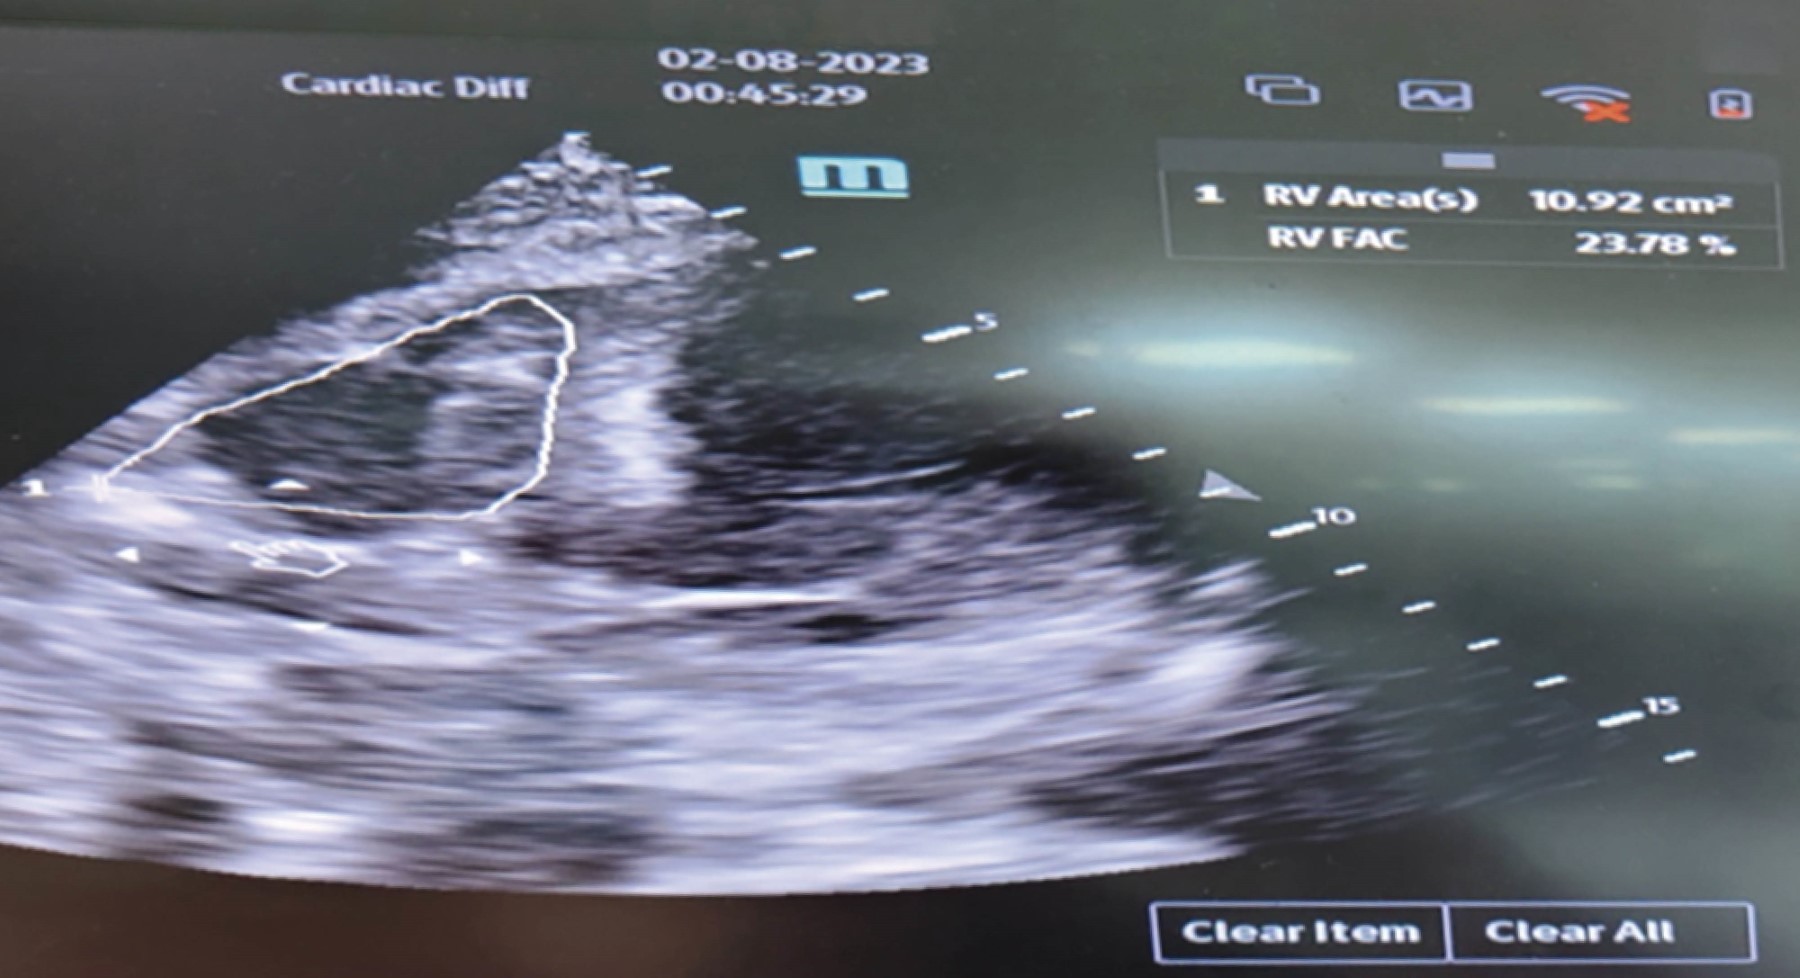

Tako-tsubo syndrome in older adults

Tako-tsubo syndrome is characterized by transient regional systolic dysfunction, mainly of the left ventricle, which can be confused with an acute myocardial infarction. Still, without angiographic evidence of obstructive coronary artery disease, it is triggered by a stress episode. Its highest incidence is in postmenopausal women; in men over 70 years old, it is rare and has higher mortality.

Figure 2